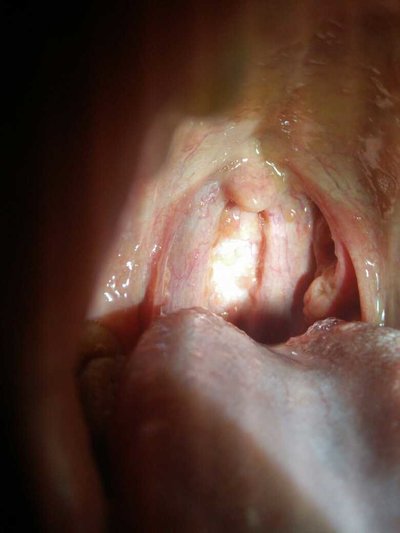

Examination showed congestion and swelling of pharyngeal mucosa, dark red, increased secretion. The mucosa of pharyngopalatal arch swelled. The lymphoid follicles in the posterior pharyngeal wall were swollen and congested. The soft palate and tonsils are also congested. Sometimes we can see uvula dropsy and soft palate swelling. In patients with severe infection, the pharyngeal lymph cord may be red and swollen. At the same time, patients can have acute inflammatory changes of nasal mucosa. When the neck pain may touch the swelling lymph node, has the tenderness.